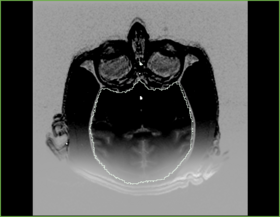

Before - After subtract image

Recovered bias field